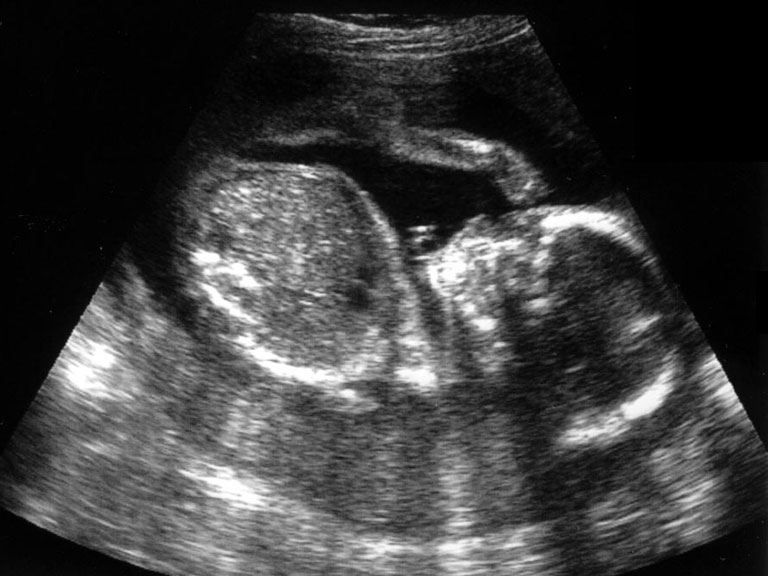

2분기 (임신 14주부터 28주)와 3분기 (임신 28주부터 출산까지)

1. 태아의 수

2. 태아의 선진부 (즉 머리가 산모의 골반쪽에 위치하는지 배꼽 쪽에 위치하는지 여부)

3. 태아의 생존 여부 즉 심박동 유무와 횟수 확인

4. 태반의 위치

5. 양수의 양

6. 태아 머리둘레와 대퇴골, 복부 측정으로 태령 및 태아 체중 예상

7. 제대의 착상 부와 혈관 구조 확인

8. 태아의 해부학적 구조 확인--뇌실, 심장, 척추, 위, 방광, 복벽, 신장등

9. 태아의 호흡이나 운동성 확인

10. 자궁과 그 부속기인 난소등 검사